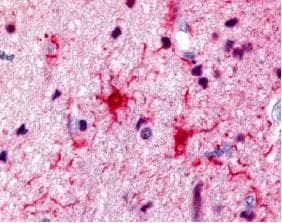

Rabbit Polyclonal S10A1 antibody. Suitable for WB, IHC-P and reacts with Cow, Rat, Mouse, Human samples. Cited in 10 publications. Immunogen corresponding to Native Full Length Protein corresponding to Cow Protein S100-A1.

Applications IHC-P, WB

Species Reactivity Cow, Human, Mouse, Rat